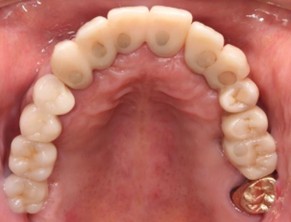

10代 男性

治療前

治療後

治療後- 年齢/性別

- 10代/男性

- 主訴

- 上顎前歯部咬合痛歯根破折

- 治療期間

- 11ヶ月

- 治療費

- インプラント¥880,000

骨造成¥130,000

サージカルステント¥77,000 - リスク・副作用

- 術後の腫脹 出血